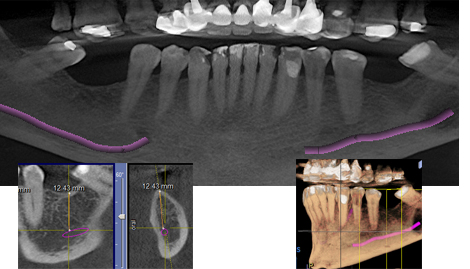

Vemos en las imágenes de este caso la gran utilidad diagnóstica de la TVD: el paciente relata dolor en 3.7 y la radiografía periapical no muestra ninguna lesión; se indicó una tomografía volumétrica digital y vemos una profunda lesión periodontal en la raíz distal que indica un mal pronóstico sobre todo si vemos la sección transversal que tiene una mínima inserción ósea en la zona apical.

La También permite que el nervio dentario inferior y el foramen mentoniano sean claramente identificables con la TVD, lo que permite planificar los procedimientos quirúrgicos con anticipación y evaluando las zonas de riesgo y elaborar un plan de tratamiento más preciso y personalizado. Las imágenes interactivas permiten tomar mediciones de cualquier zona con absoluta precisión.